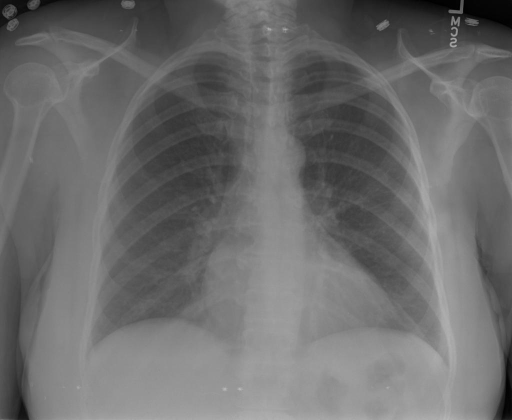

## 本文贡献  - 借助ChatGPT以及公开的数据集,我们构造了一个`X光影像-诊断报告`对的医学多模态数据集; - 我们将构建的中文胸部X光片诊断数据集在[VisualGLM-6B](https://github.com/THUDM/VisualGLM-6B)进行微调训练,并开放了部分训练权重用于学术研究; ## 数据集 - [MIMIC-CXR](https://physionet.org/content/mimic-cxr-jpg/2.0.0/)是一个公开可用的胸部X光片数据集,包括377,110张图像和227,827个相关报告。 - [OpenI](https://openi.nlm.nih.gov/faq#collection)是一个来自印第安纳大学医院的胸部X光片数据集,包括6,459张图像和3,955个报告。 在上述工作中,报告信息都为非结构化的,不利于科学研究。为了生成合理的医学报告,我们对两个数据集进行了预处理,并最终得到了可以用于训练的**英文报告**。除此之外,为了更好的支持中文社区发展,借助ChatGPT的能力,我们将英文报告进行了中文翻译,并最终形成了可用于训练的数据集。 |数据集|数量|下载链接| |:-|:-|:-| |MIMIC-CXR-zh|-|-| |OpenI-zh|6,423|[诊疗报告(英文)](./data/openi-en.json)、[诊疗报告(中文)](./data/Xray/openi-zh.json) 、[X光影像](https://pan.baidu.com/s/13GBsDMKf6xBZBSHpoWH_EA?pwd=k9sh)| ## 快速上手 1. 安装环境 ```bash # 安装依赖 pip install -r requirements.txt # 国内换源安装依赖 pip install -i https://mirrors.aliyun.com/pypi/simple/ -r requirements.txt ``` 此时默认会安装`deepspeed`库(支持`sat`库训练),此库对于模型推理并非必要,同时部分`Windows`环境安装此库时会遇到问题。 如果想绕过`deepspeed`安装,我们可以将命令改为: ```bash # 安装依赖 pip install -i https://mirrors.aliyun.com/pypi/simple/ -r requirements_wo_ds.txt # 安装SwissArmyTransformer pip install -i https://mirrors.aliyun.com/pypi/simple/ --no-deps "SwissArmyTransformer>=0.3.6" ``` 2. 模型推理 |模型权重|下载链接| |:-|:-| |checkpoints-XrayGLM-300|-| |checkpoints-XrayGLM-3000|-| CLI推理: ```python python cli_demo.py --from_pretrained checkpoints/checkpoints-XrayGLM-3000 --prompt_zh '详细描述这张胸部X光片的诊断结果' ``` 更多[参数](https://github.com/WangRongsheng/XrayGLM/blob/main/cli_demo.py#L16) ## 效果展示 影像诊断: |X光影像|诊疗报告(医生)|XrayGLM| |:-|:-|:-| ||根据X射线图像,心脏大小正常,肺部看起来很清晰。已经排除了肺炎、积液、水肿、气胸、腺病、结节或肿块的存在。该发现表明一切正常。换句话说,总体印象是胸部正常。|X光片显示,心脏大小正常。肺部没有气胸或胸腔积液的证据。骨骼结构看起来没有任何异常。总的来说,X光片表明没有发现急性心肺疾病的迹象。| ||X光图片显示没有扭曲的区域、可疑的骨质不透明度或胸腺积液。心脏大小轻微增大,但非常稳定。此外,没有气胸的证据,肺野也正常。总体来说,X光片显示没有急性心脏异常,但要注意轻微的心脏扩大。|X光片显示,心脏大小正常。肺部和纵隔轮廓清晰,没有气胸或胸腔积液的证据。骨骼结构完整,没有任何急性异常。| ||心影形态在正常范围内。没有急性骨质异常。有可能出现没有明显的吸水或肺实质状况的线索。没有大面积积液或气胸。有可能怀疑其有误吸或肺实质问题。为了确诊和治疗,可能需要进行适当的影像学随访。|心脏大小正常,肺部和纵隔轮廓清晰。没有急性异常或活动受限的证据。没有任何明显的气胸、胸腔积液或肺不张的迹象。此外,也没有发现任何局灶性骨质异常或其他急性疾病。| 多轮对话: |X光影像|诊疗报告(医生)| |:-|:-| ||右侧主动脉突出观察到。心脏大小正常。胸部未发现明显的肺气肿、胸膜积液或可疑的肺部病变。报告指出已知右侧主动脉情况正常。| ```bash >> X光影像路径:./data/Xray/861_1.png >> 用户:这是一张什么图? >> XrayGLM:这张图片显示的是一张肺部检查的X光片。 >> 用户:请描述这张胸部X光片的诊断结果 >> XrayGLM:心脏大小正常,肺部清晰。没有急性心肺疾病的证据。 >> 用户:是否存在肺气肿? >> XrayGLM:没有肺气肿。心脏大小正常,肺部清晰。没有发现急性心肺疾病的证据。 >> 用户:平时饮食该注意什么? >> XrayGLM:饮食应该健康,均衡。建议增加蛋白质的摄入量,因为蛋白质有助于维持肌肉和骨骼的健康。多食用蔬菜、水果、全谷物以及健康的脂肪来源如橄榄油、鱼类等可以帮助获得足够的维生素和矿物质。此外,避免过度饮酒或吸烟,这些习惯可能会对心脏健康产生负面影响。 ``` ## 未来展望 1. 模型的能力更多来源于数据的支持,`OpenI-zh`作为微调数据集,其数据量足以支持研究,在更广泛的任务和性能表现上,我们认为**在大规模数据集上预训练并在高质量少量数据集上微调是一种可行的方案**; 2. 普遍意义的理解上,视觉多模态模型=视觉模型+语言模型。除了需要关注视觉模型信息与语言模型输出的搭配外,还需要**额外关注到语言模型的加强,在人机的对话中,尤其是医疗语言模型的问答上,除了专业的医疗问题回答,带有人文情怀的有温度的回答更应该是我们追寻的目标**。 ## 项目致谢 1. [VisualGLM-6B](https://github.com/THUDM/VisualGLM-6B)为我们提供了基础的代码参考和实现; 2. [MiniGPT-4](https://github.com/Vision-CAIR/MiniGPT-4)为我们这个项目提供了研发思路; 3. ChatGPT生成了高质量的中文版X光检查报告以支持XrayGLM训练; 4. [gpt_academic](https://github.com/binary-husky/gpt_academic)为文档翻译提供了多线程加速; 5. [MedCLIP](https://github.com/RyanWangZf/MedCLIP) 、[BLIP2](https://huggingface.co/docs/transformers/main/model_doc/blip-2) 、[XrayGPT](https://github.com/mbzuai-oryx/XrayGPT) 等工作也有重大的参考意义;  这项工作由[澳门理工大学应用科学学院](https://www.mpu.edu.mo/esca/zh/index.php)硕士生[王荣胜](https://github.com/WangRongsheng) 、[段耀菲](https://github.com/IsBaSO4) 、[李俊蓉](https://github.com/lijunrong0815)完成,指导老师为檀韬副教授、[彭祥佑](http://www.patrickpang.net/)老师。 *特别鸣谢:[USTC-PhD Yongle Luo](https://github.com/kaixindelele) 提供了有3000美金的OpenAI账号,帮助我们完成大量的X光报告翻译工作 ## 免责声明 本项目相关资源仅供学术研究之用,严禁用于商业用途。使用涉及第三方代码的部分时,请严格遵循相应的开源协议。模型生成的内容受模型计算、随机性和量化精度损失等因素影响,本项目无法对其准确性作出保证。即使本项目模型输出符合医学事实,也不能被用作实际医学诊断的依据。对于模型输出的任何内容,本项目不承担任何法律责任,亦不对因使用相关资源和输出结果而可能产生的任何损失承担责任。 ## 项目引用 如果你使用了本项目的模型,数据或者代码,请声明引用: ```bash @misc{wang2023XrayGLM, title={XrayGLM: The first Chinese Medical Multimodal Model that Chest Radiographs Summarization}, author={Rongsheng Wang, Yaofei Duan, Junrong Li, Patrick Pang and Tao Tan}, year={2023}, publisher = {GitHub}, journal = {GitHub repository}, howpublished = {\url{https://github.com/WangRongsheng/XrayGLM}}, } ``` ## 使用许可 此存储库遵循[CC BY-NC-SA](https://creativecommons.org/licenses/by-nc-sa/4.0/) ,请参阅许可条款。